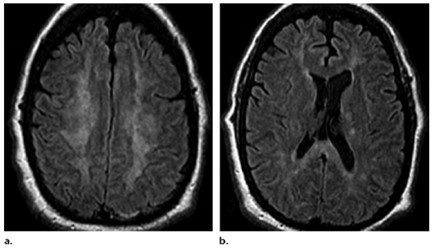

En relación con este tipo de drogas, se puede citar el reporte de un caso de intoxicación de un varón de 16 años por consumo de píldoras de oxicodona. La TC permitió visualizar la hipodensidad en núcleos caudados, así como una rabdomiólisis de etiología inflamatoria o infecciosa (ver Imagen 14). El paciente presentó otros signos como escasa coordinación, pérdida de conocimiento y dificultad para respirar, que se resolvió en pocos días con intubación y asistencia ventilatoria.(23)

En el caso que se viene ilustrando, la RM mostró T2 difuso con hiperintensidades en el cuerpo calloso bilateral frontal y parietal, así como lesión difusa de la sustancia blanca del cerebelo. Se localizaron áreas de difusión restringida en los ganglios basales bilaterales, lo cual tenía relación con la pérdida neuronal mediada por estrés oxidativo (ver Imágenes 15 y 16). El tratamiento permitió la recuperación progresiva del habla y la orientación de la persona. (23)